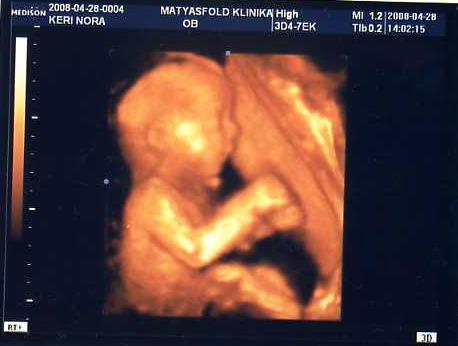

ZÁRT A MÉHSZÁJ!!!!!!!!!!!!!!!!!!!!!!!! Annyira örültem, ez most nekem ezerszer fontosabb hír volt minden ajándéknál!!!!

Aztán voltam Uh-on, Simike nagyon édes, egész végig szopizott, de úgy, hogy nagyon elszántan próbálta gyömöszkélni mindkét kezét a szájacskájába, végignevettük a szonográfussal az egészet! Ismét napra pontosan saccol a gép, ezen mindig meglepődünk!